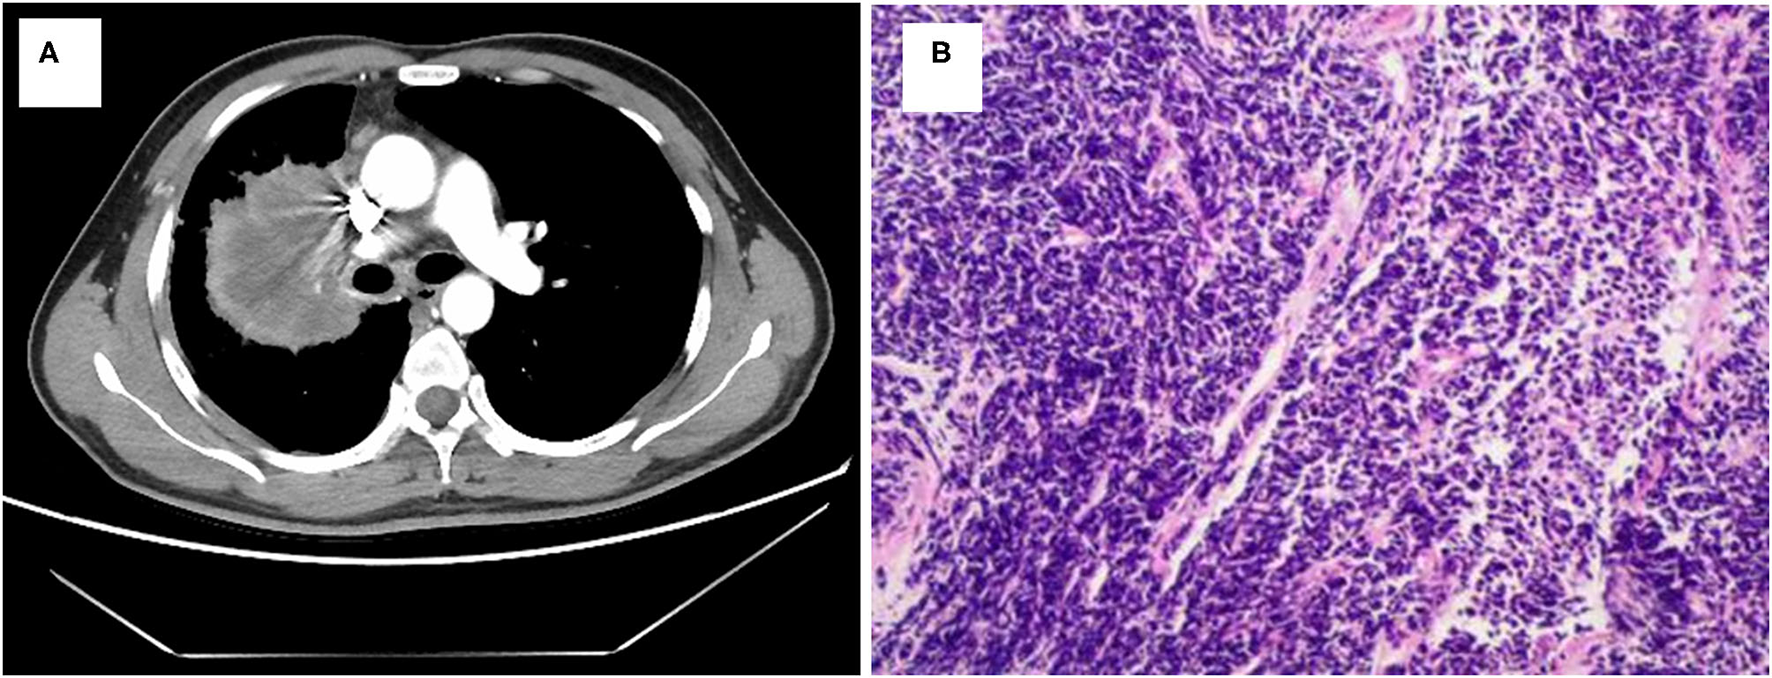

A 40-year-old smoking man presented to our hospital complaining of a 5-month history of aggravating and irritating dry cough in April 2019. In 1999, he underwent surgery for ulna fracture. He denied other prior disease and family history. Percussion of right upper lung showed solid sound, and auscultation suggested that the right lung breath sound was weak. The chest computed tomography (CT) showed a mass in the right lung (7.6 cm × 5.8 cm) with multiple enlarged lymph nodes in mediastinum (Figures 1A, 2). Magnetic resonance imaging (MRI) did not find any significant space-occupying lesions in the brain. Percutaneous lung biopsy was performed, and atypical cells were observed (Figure 1B). Immunohistochemical staining showed positive expression for thyroid transcription factor-1 (TTF-1), cytokeratin (CK) 8/18, and CK7, as well as negative expression for CK5/6, novel aspartic proteinase A (Napsin A), and P40. Pathological findings of the lung biopsy established the diagnosis of lung low-differentiated adenocarcinoma. Finally, his disease was diagnosed as right lung adenocarcinoma (T3N2M0, IIIA).

Figure 1

Lung adenocarcinoma shown by radiologic and pathologic examinations. (A) Chest CT scan reveals a mass in right lung. (B) Hematoxylin and eosin staining shows a low differentiation adenocarcinoma (HE × 100).